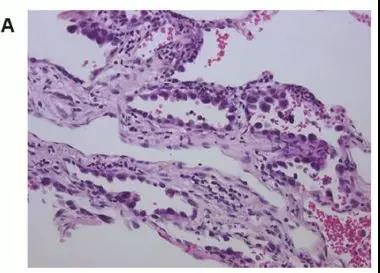

图A,病理检查肿瘤周边没有STAS

图B,病理检查发现肿瘤周边有1-4个癌细胞或癌巢,属于低STAS

图C,病理检查发现肿瘤周边有超过5个癌细胞或癌巢,属于高STAS